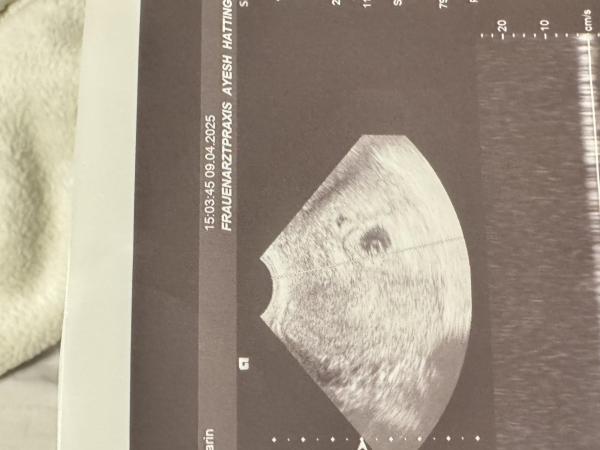

Ich bin 22 Jahre jung und habe im Dezember 2020 einen wundervollen Jungen zuhause entbunden. Für uns stand sofort fest, dass wir ihn nicht lange auf ein Geschwisterchen warten lassen wollen ![]() nun bin ich erneut schwanger und wir waren auch schon beim FA. Ich bin nun auf die Ramzi Methode gestoßen und habe mich gefragt, ob jemand davon irgendwie Ahnung hat und aus dem Ultraschallbild eventuell sagen kann, was es wohl wird

nun bin ich erneut schwanger und wir waren auch schon beim FA. Ich bin nun auf die Ramzi Methode gestoßen und habe mich gefragt, ob jemand davon irgendwie Ahnung hat und aus dem Ultraschallbild eventuell sagen kann, was es wohl wird ![]() ich glaube zwar nicht an sowas, aber so kriegt man die Zeit bis zum nächsten Termin rum.

Laut Ramzi Methode würde es ein Junge sein, wenn der Ultraschall vaginal entstanden ist, aber wer weis ob das stimmt ![]()

Also wenn vaginal schall dann bei kleeblatt ein Junge.